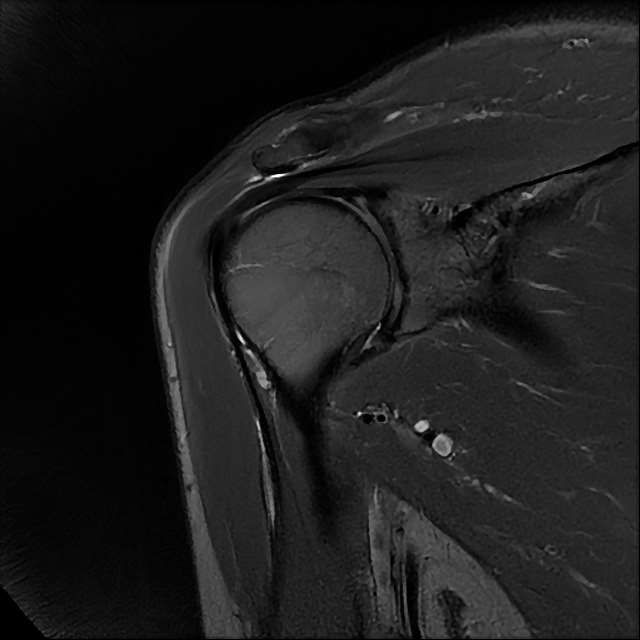

오른쪽 어깨 와순파열 및 점액낭염이 보인다고 하는데 상태를 알고 싶습니다

MRI 사진상 와순파열 점액낭염 등이 있다고 하는데..심한 상태인가요?

MRI상 와순파열, 회전근개 부분파열 등이 있으며 일부 염증소견이 있습니다.

주사, 약물, 물리치료 등에 통증이 호전을 보인다면 경과관찰을 해볼 수도 있겠지만 어깨관절의 불안정성 및 통증이 심하신 상태라면 관절경을 이용하여 수술적 치료를 받으시는 것을 추천드립니다.